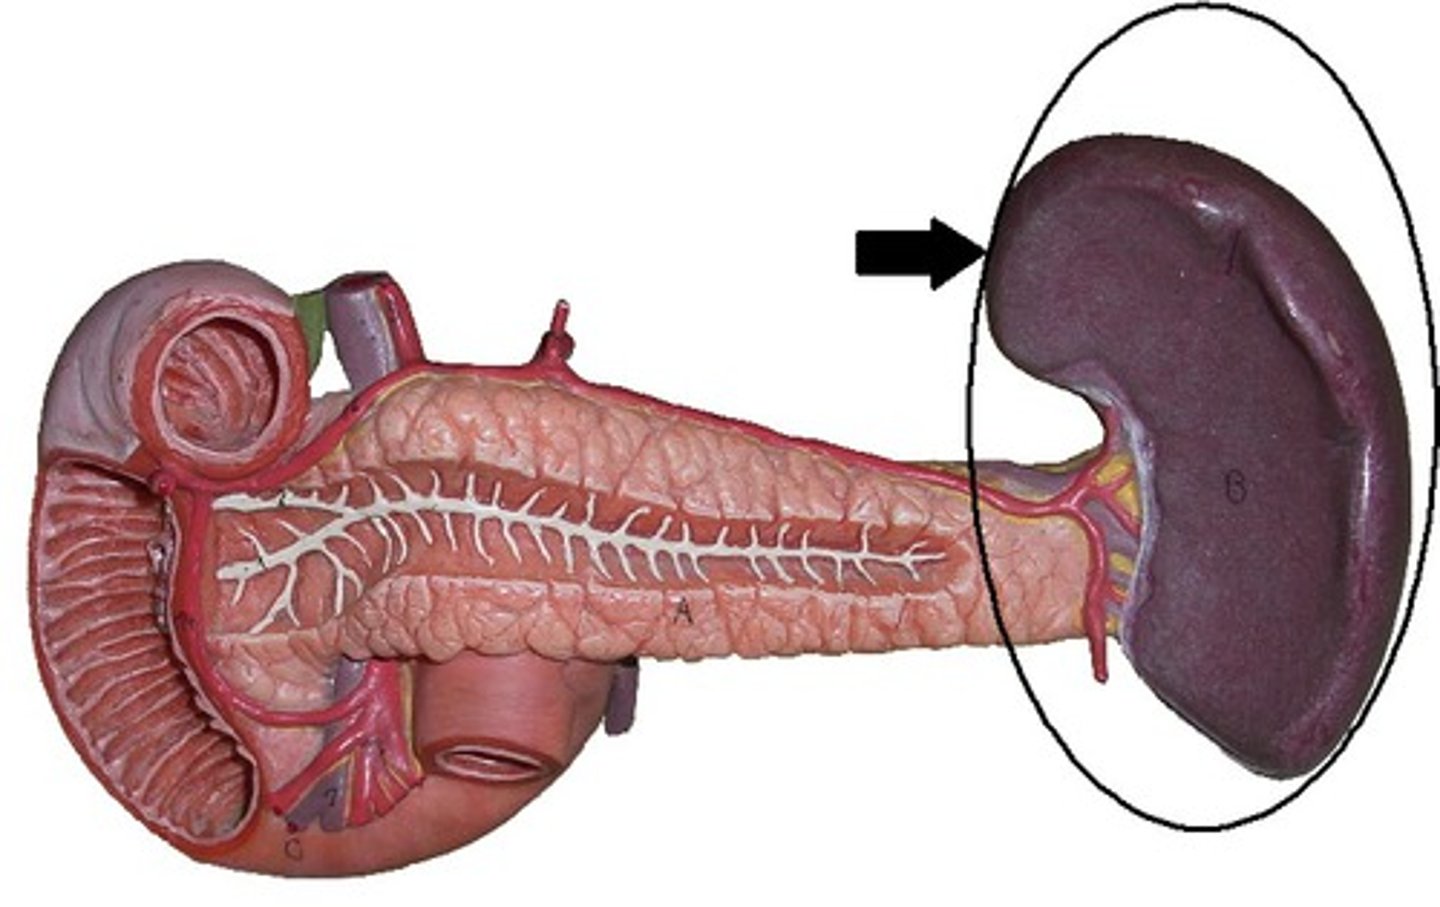

spleen